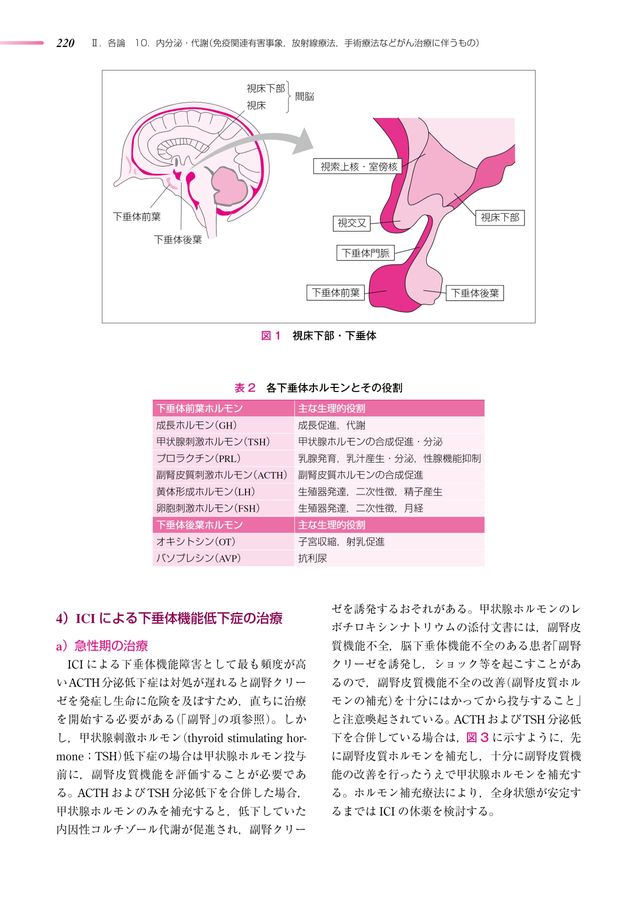

NET・下垂体・副甲状腺・副腎 (腫瘍病理鑑別診断アトラス, m3電子書籍 | 腫瘍病理鑑別診断アトラス NET・下垂体・副甲状腺,

m3電子書籍 | 腫瘍病理鑑別診断アトラス NET・下垂体・副甲状腺, m3電子書籍 | 腫瘍病理鑑別診断アトラス NET・下垂体・副甲状腺,

71Ksd2S6uPL.jpg, 朝倉書店『内科学』(第12版)デジタル付録,